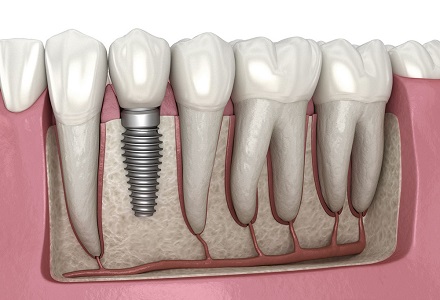

We offer a wide range of services to help you achieve and maintain a healthy and beautiful smile. Our team of experienced and skilled dental professionals is committed to providing you with the highest quality of care in a comfortable and welcoming environment.

Why Choose 4th Street Dental Clinic? Exceptional dental care in a comfortable and welcoming environment, Experienced and compassionate dental professionals, Personalized care for each patient, Commitment to preventative care and education, Use of the latest technology and techniques and Affordable dental care for everyone